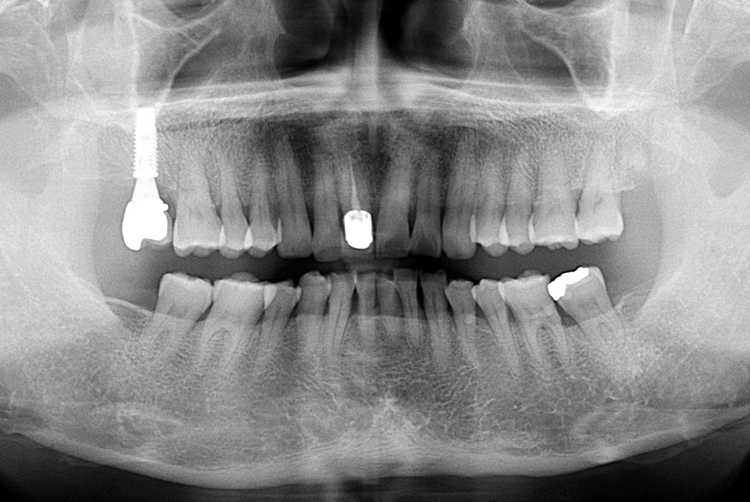

[임플란트] 어금니 임플란트

치료전 : 2017-07-04

세종치과는 많은 환자와 다양한 케이스를 바탕으로

항상 편안한 임플란트 수술을 제공하고자 노력하고,

오래동안 튼튼히 쓸 수 있는 임플란트 수술을 가장 큰 목표로 삼고 있습니다.